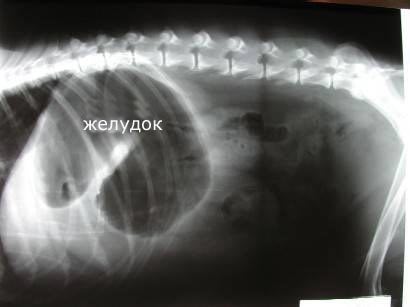

Заворот желудка

Остро протекающее заболевание, характерное преимущественно для собак крупных и гигантских пород, сопровождающееся быстрым (в течение нескольких часов) увеличением объема живота и прогрессивным ухудшением состояния собаки вплоть до гибели.

Как выглядит заворот желудка?

Ухудшение состояния происходит на фоне внешнего благополучия, чаще у плотно поевших собак после активной прогулки.

Животное начинает беспокойно себя вести, стонет, не может найти себе место.

Можно наблюдать слюнотечение, безуспешные попытки к рвоте, значительное увеличение живота в объеме, одышку, при постукивании по брюшной стенке в области последнего ребра слева слышен тимпанический (как при ударе в барабан) звук.

На более поздних стадиях (уже через 1-2 часа!) явления расстройства дыхания нарастают, возникает тахикардия (частое сердцебиение), возникает слабость вначале задних, затем передних лап, температура, как правило, снижается, слизистые оболочки бледные.